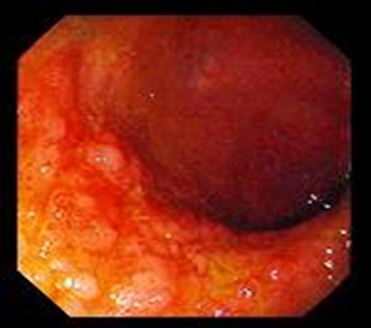

Klinika. Çox rəngarəngdir. Diareya və sorulma pozğunluqlarına görə çəki itkisi kardinal simptomdur. İshalsız gediş zamanı oynaq ağrıları (iltihablı və iltihabsız klinik gediş), yağlı və ya qanlı nəcis ifrazı, qarında spazmlar, köp, qızdırma, yorğunluq, dərinin tündləşməsi, iştahın azalması, limfa düyünlərinin böyüməsi, NB-ın selikli qişasında anomal sarı və ağ ləkələrin (endoskopik görünüş) əmələ gəlməsi kimi fərqli əlamətlər müşahidə olunur.